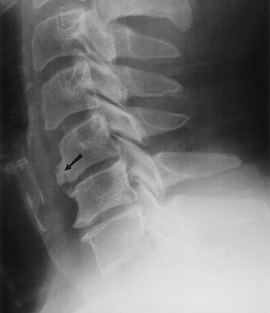

FIGURE 3-56 Discitis. Lateral radiograph shows loss of disc height and early endplate irregularity at L1–2 (arrow). Note the normal disc below.

|